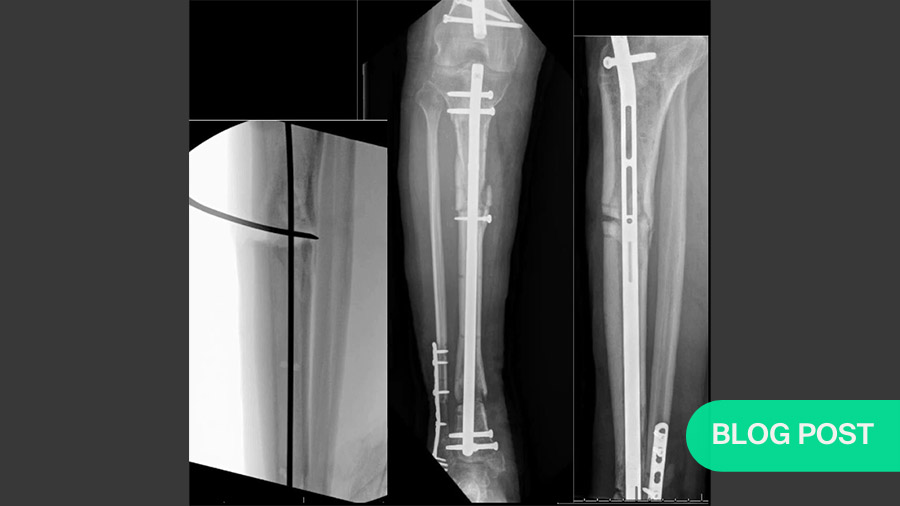

Meta- and diaphyseal tibial bone loss is quite rare in orthopedic trauma, making it difficult to set up large-scale studies. Its most common causes are trauma, infection or the excision of tumors. Complications—especially infection—can lead to long-term loss of function or amputation. And while various treatments are available, no consensus yet exists regarding which are most effective.

Masquelet’s induced membrane technique (Masquelet’s technique, a Masquelet, the induced membrane technique, induced membrane) is a two-step process that can be used to stimulate high-quality bone regeneration even for massive (>15cm) bone loss or other defects . While it is also commonly used to lengthen short but otherwise healthy limbs, the current discussion focuses on defects resulting from trauma, infection or excision of tumors.

Lee’s third case study highlights a case where, for a short tibial defect, he decided to use a transport nail and distraction osteogenesis instead of Masquelet’s technique. While Bernstein notes that this would be prohibitively expensive for many hospitals, he also praises it as “aggressively intelligent” and highly effective. Lee supports this evaluation with a video of the patient walking well after only three months.